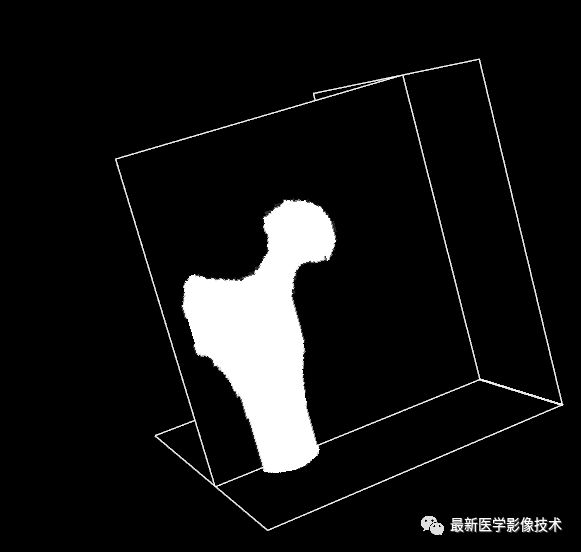

最后出入原始图像,前景Mask图像和背景Mask图像,运行后最终输出的分割结果Mask图像如图所示。